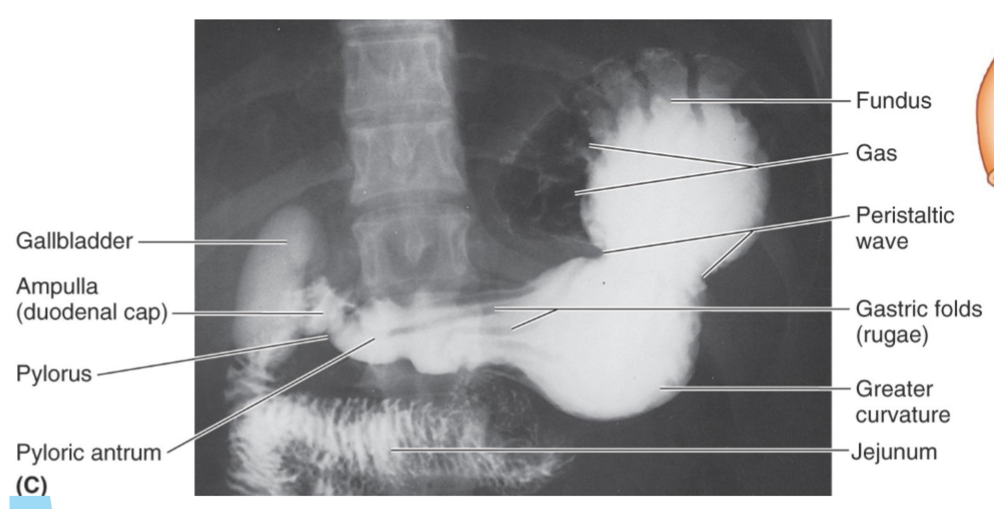

Label the coronary angiogram